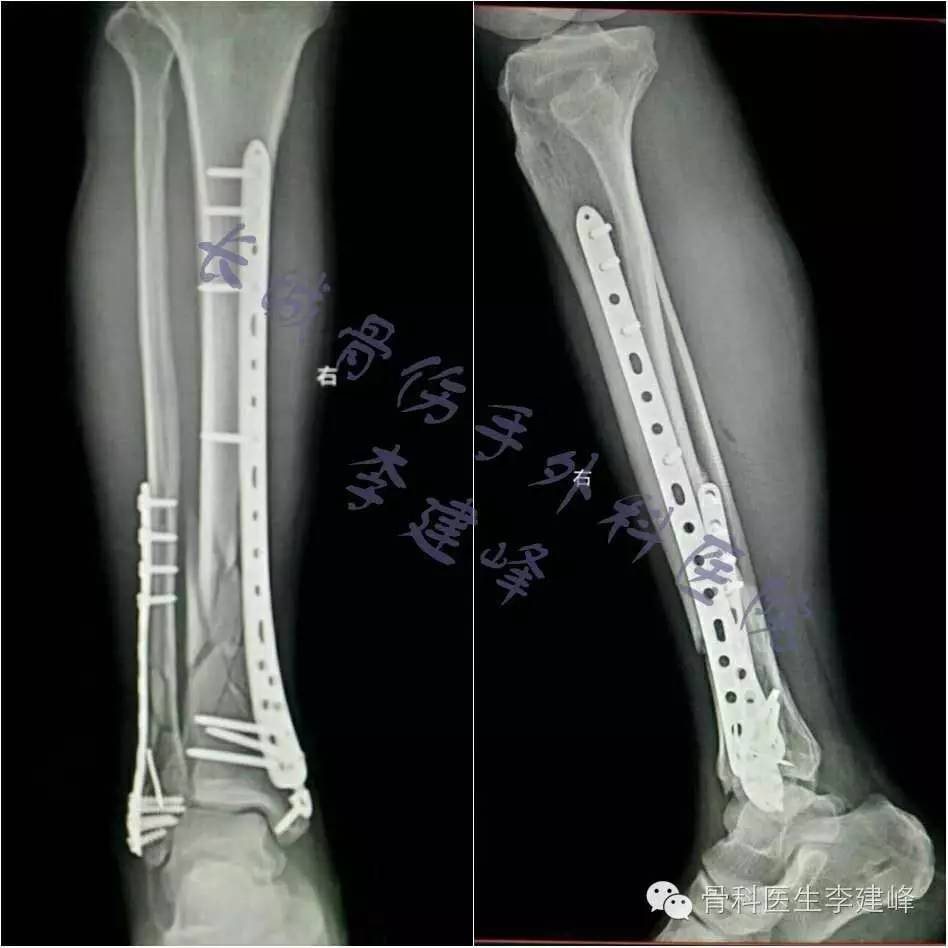

手术前照片 胫骨粉碎性骨折 腓骨骨折 网友供图 虾米图客